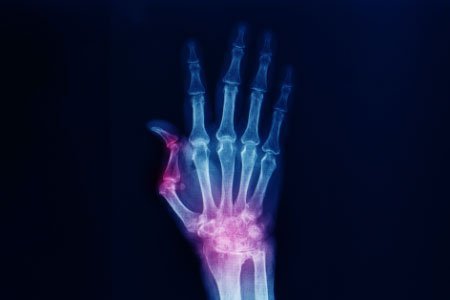

Boutonniere Deformity

Causes, Symptoms, Complications, Prevention, Diagnosis and Treatment

Boutonniere Deformity Symptoms

The symptoms of this condition may present themselves immediately after the injury or after a period of up to 3 weeks. Some of these symptoms are:

- The middle joint finger cannot be straightened

- The fingertip cannot be bent

- Swelling and pain in the affected area